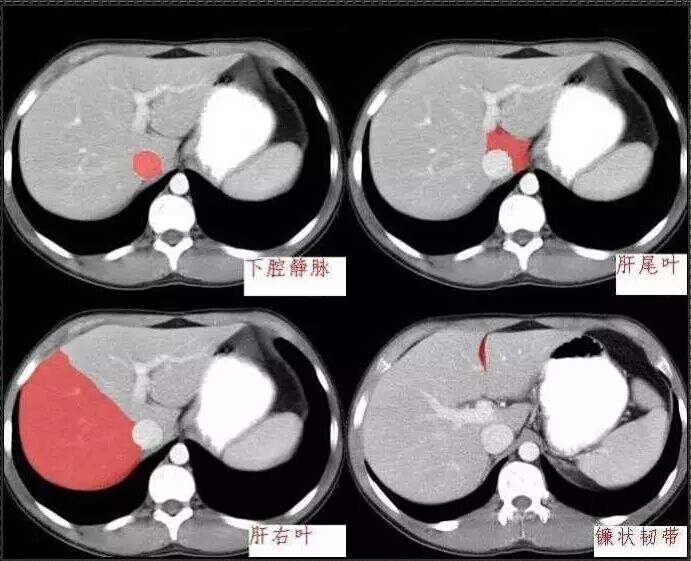

十分钟学会腹部CT解剖(多图)